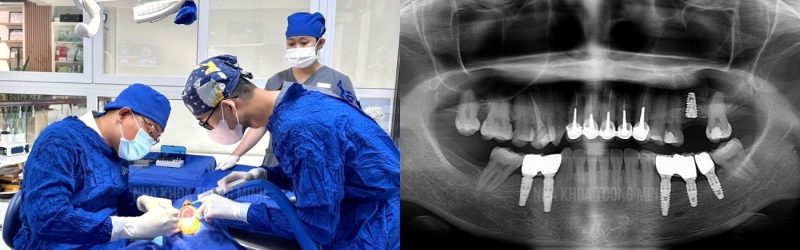

2. Bác sĩ có chuyên môn và kinh nghiệm

Implant không chỉ là đặt trụ mà còn cần đánh giá xương, vị trí, lực nhai. Bác sĩ có kinh nghiệm sẽ giúp ca điều trị chính xác và bền vững hơn.

3. Trang thiết bị hiện đại

Hệ thống chụp phim CT 3D và phần mềm hỗ trợ giúp lên kế hoạch điều trị chi tiết, đặt Implant đúng vị trí, tăng tỷ lệ thành công.